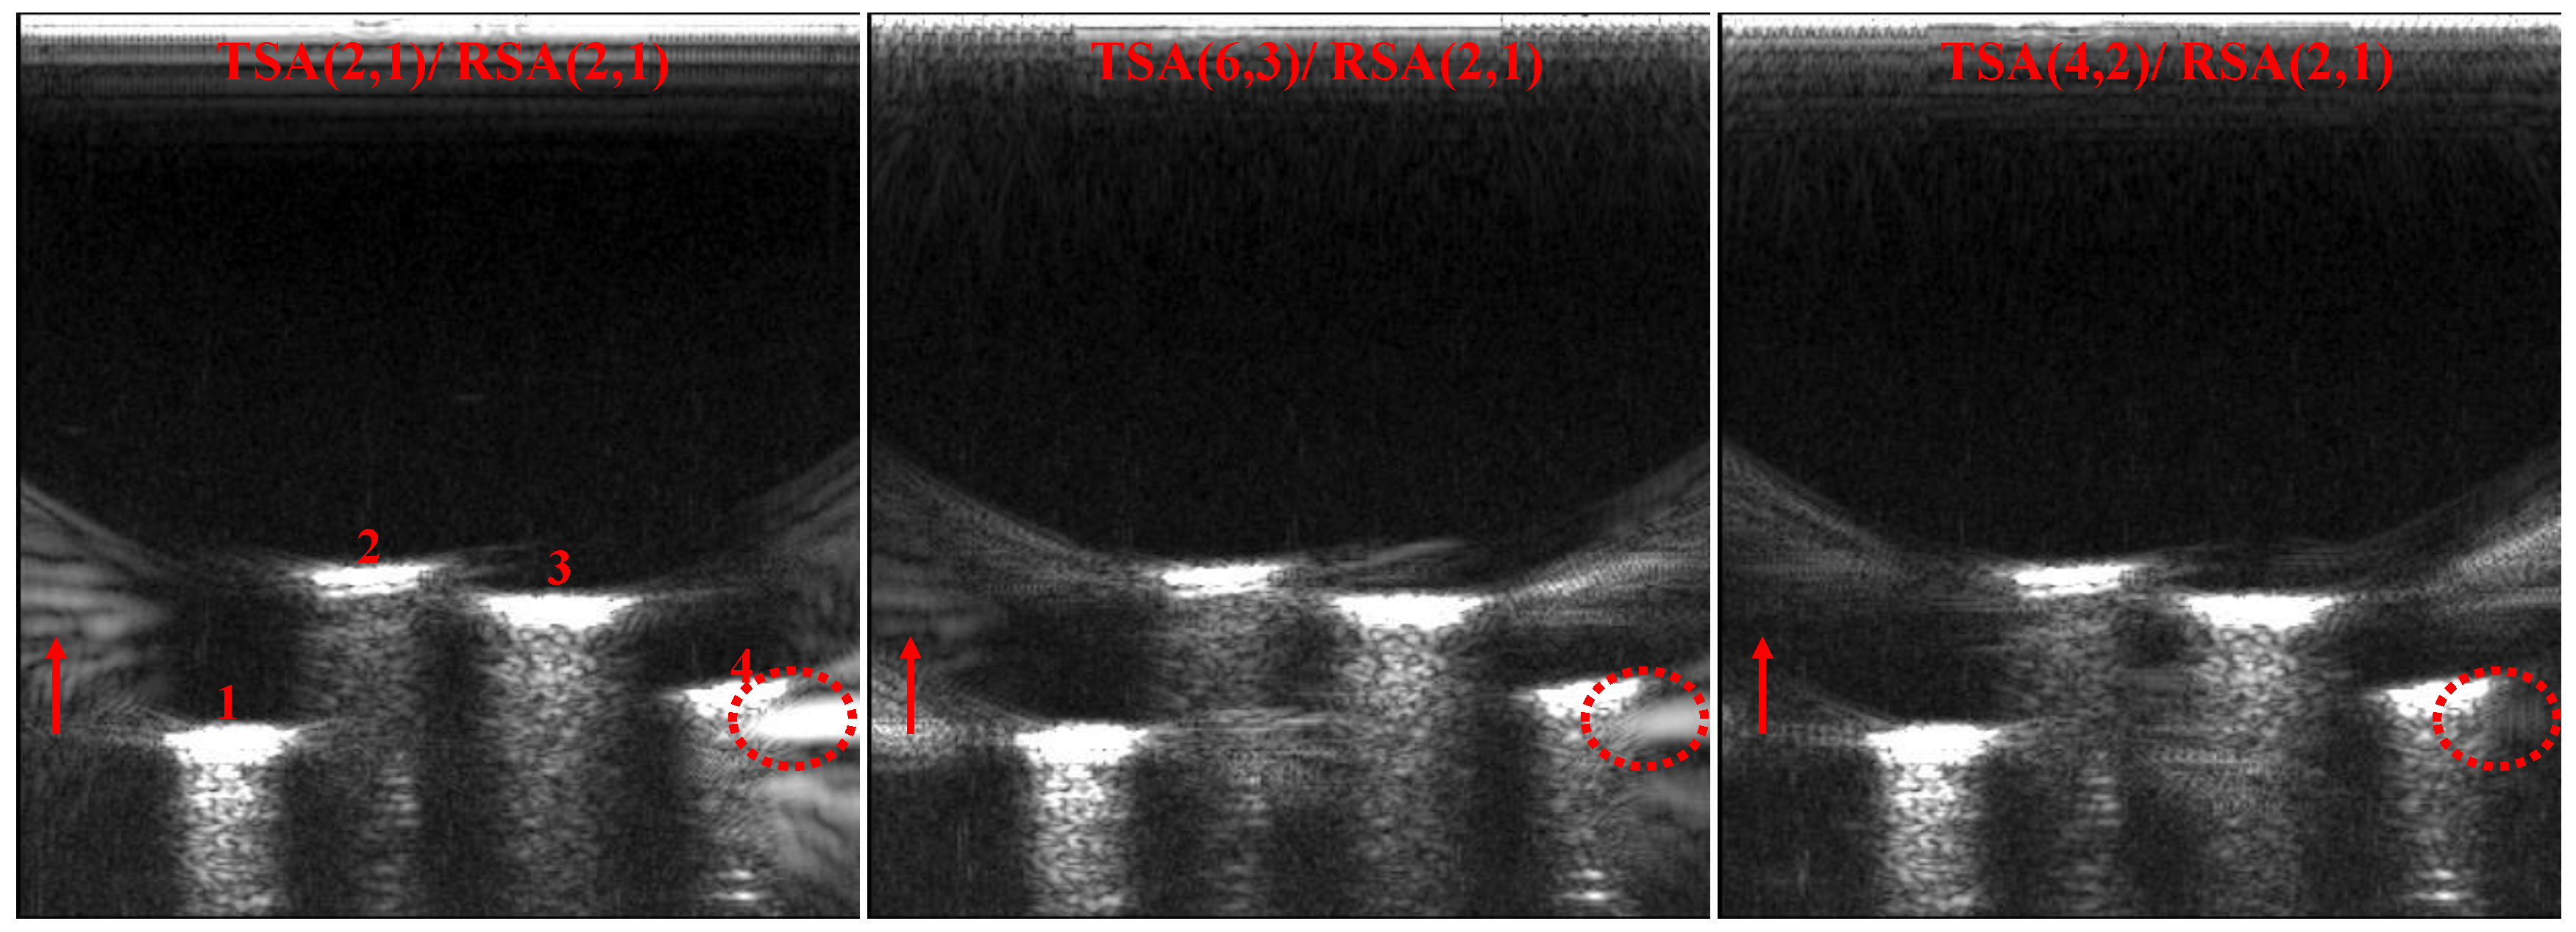

| TSA (2, 1)/RSA (2, 1) | 4369.84 | 24.33 |

| TSA (6, 3)/RSA (2, 1) | 3656.92 | 30.40 |

| TSA (4, 2)/RSA (2, 1) | 1755.90 | 33.89 |